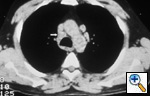

Fig. 28: Computed tomographic scan of the chest for a patient with a left sided bronchogenic carcinoma showing prominent nodes in the left prevascular region and the right paratracheal area (white arrow), suspect for N3 disease.